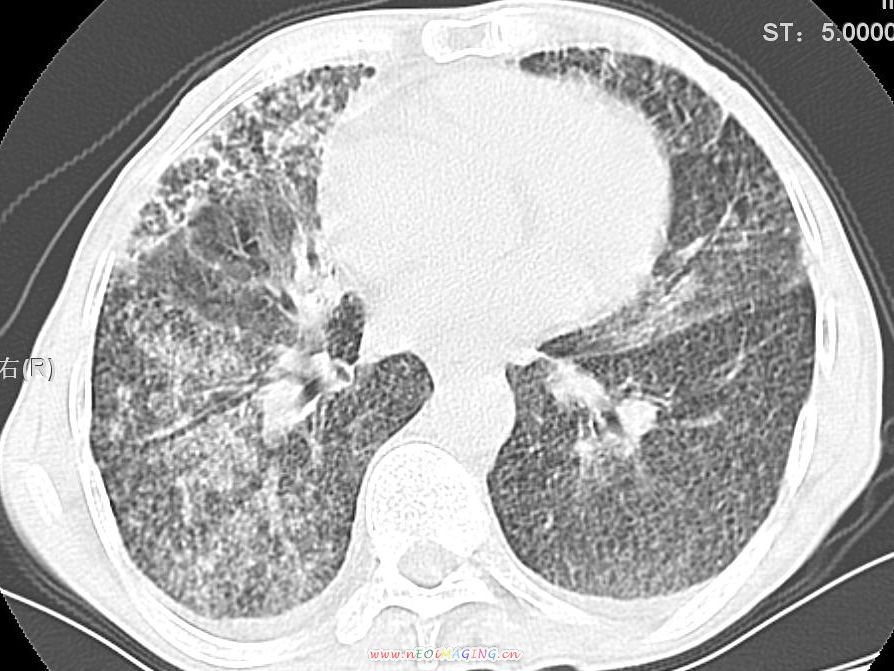

患者咳嗽月余,高热数天,咳黄色稍脓痰。

双肺野分布多个小结节状高密度影,其内散在斑片状模糊影,气管。支气管通畅,纵隔内淋巴结钙化,胸膜局限性增厚粘连,胸腔少量积液。结合病史考虑结核并感染的可能性大,胸膜炎并积液。肺泡癌待排。

纵隔内见钙化的淋巴节,上肺见钙化灶,双肺均匀弥漫分布小结节影,边缘较清楚,能不能考虑是在矽肺的基础上并发的结核和感染,请详细了解病史结合临床.